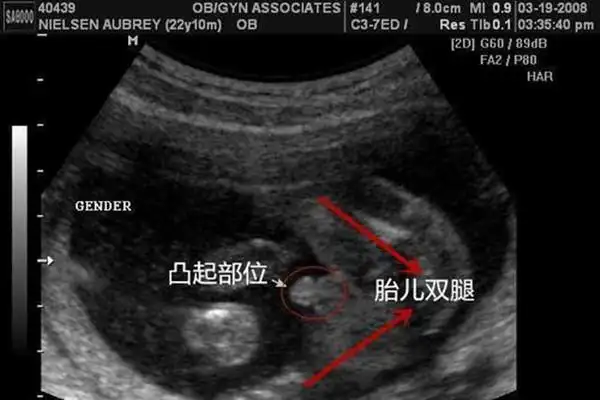

1,bpd和fl中间的差值才算是看胎儿男女的重要,但这两者的差值尺寸又和